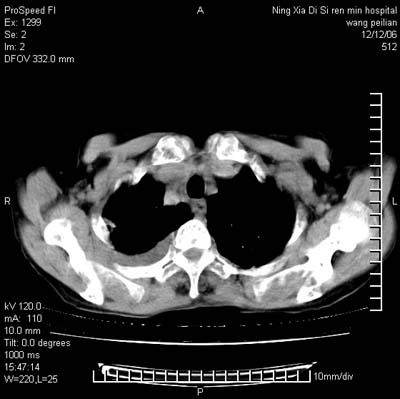

标题: CT5609:胸部:女77 病史不详 [打印本页]

标题: CT5609:胸部:女77 病史不详

两肺可见多个大小不等的结节,左侧有胸水,纵隔淋巴结增大,考虑是细支气管肺泡癌

两肺尖纤维索状影,两下肺结节块状影,且有钙化灶,右胸腔积液。考虑肺结核并胸膜炎。

两肺尖纤维索状影,两下肺结节块状影,且有钙化灶,右胸腔积液。考虑肺结核并胸膜炎肺间质纤维化

考虑:1、慢性支气管炎合并全小叶型肺气肿、间质纤维化;

2、双肺结核;

3、右侧胸膜炎(积液)。

1、双肺继发型肺结核(以纤维、增殖灶为主);

2、右侧胸腔积液;

3、其余符合老年肺改变。